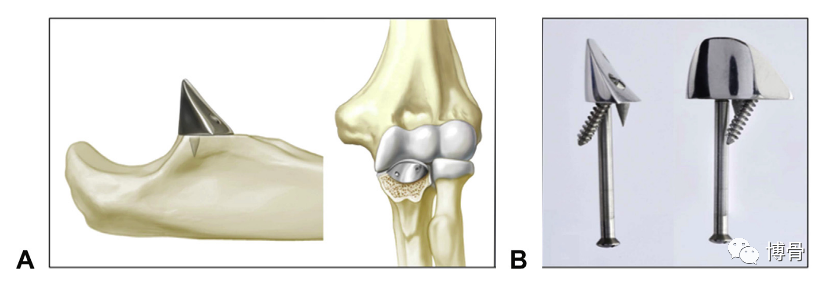

冠状突假体置换

冠状突假体置换术后11年,假体位置良好,但肘关节退变明显